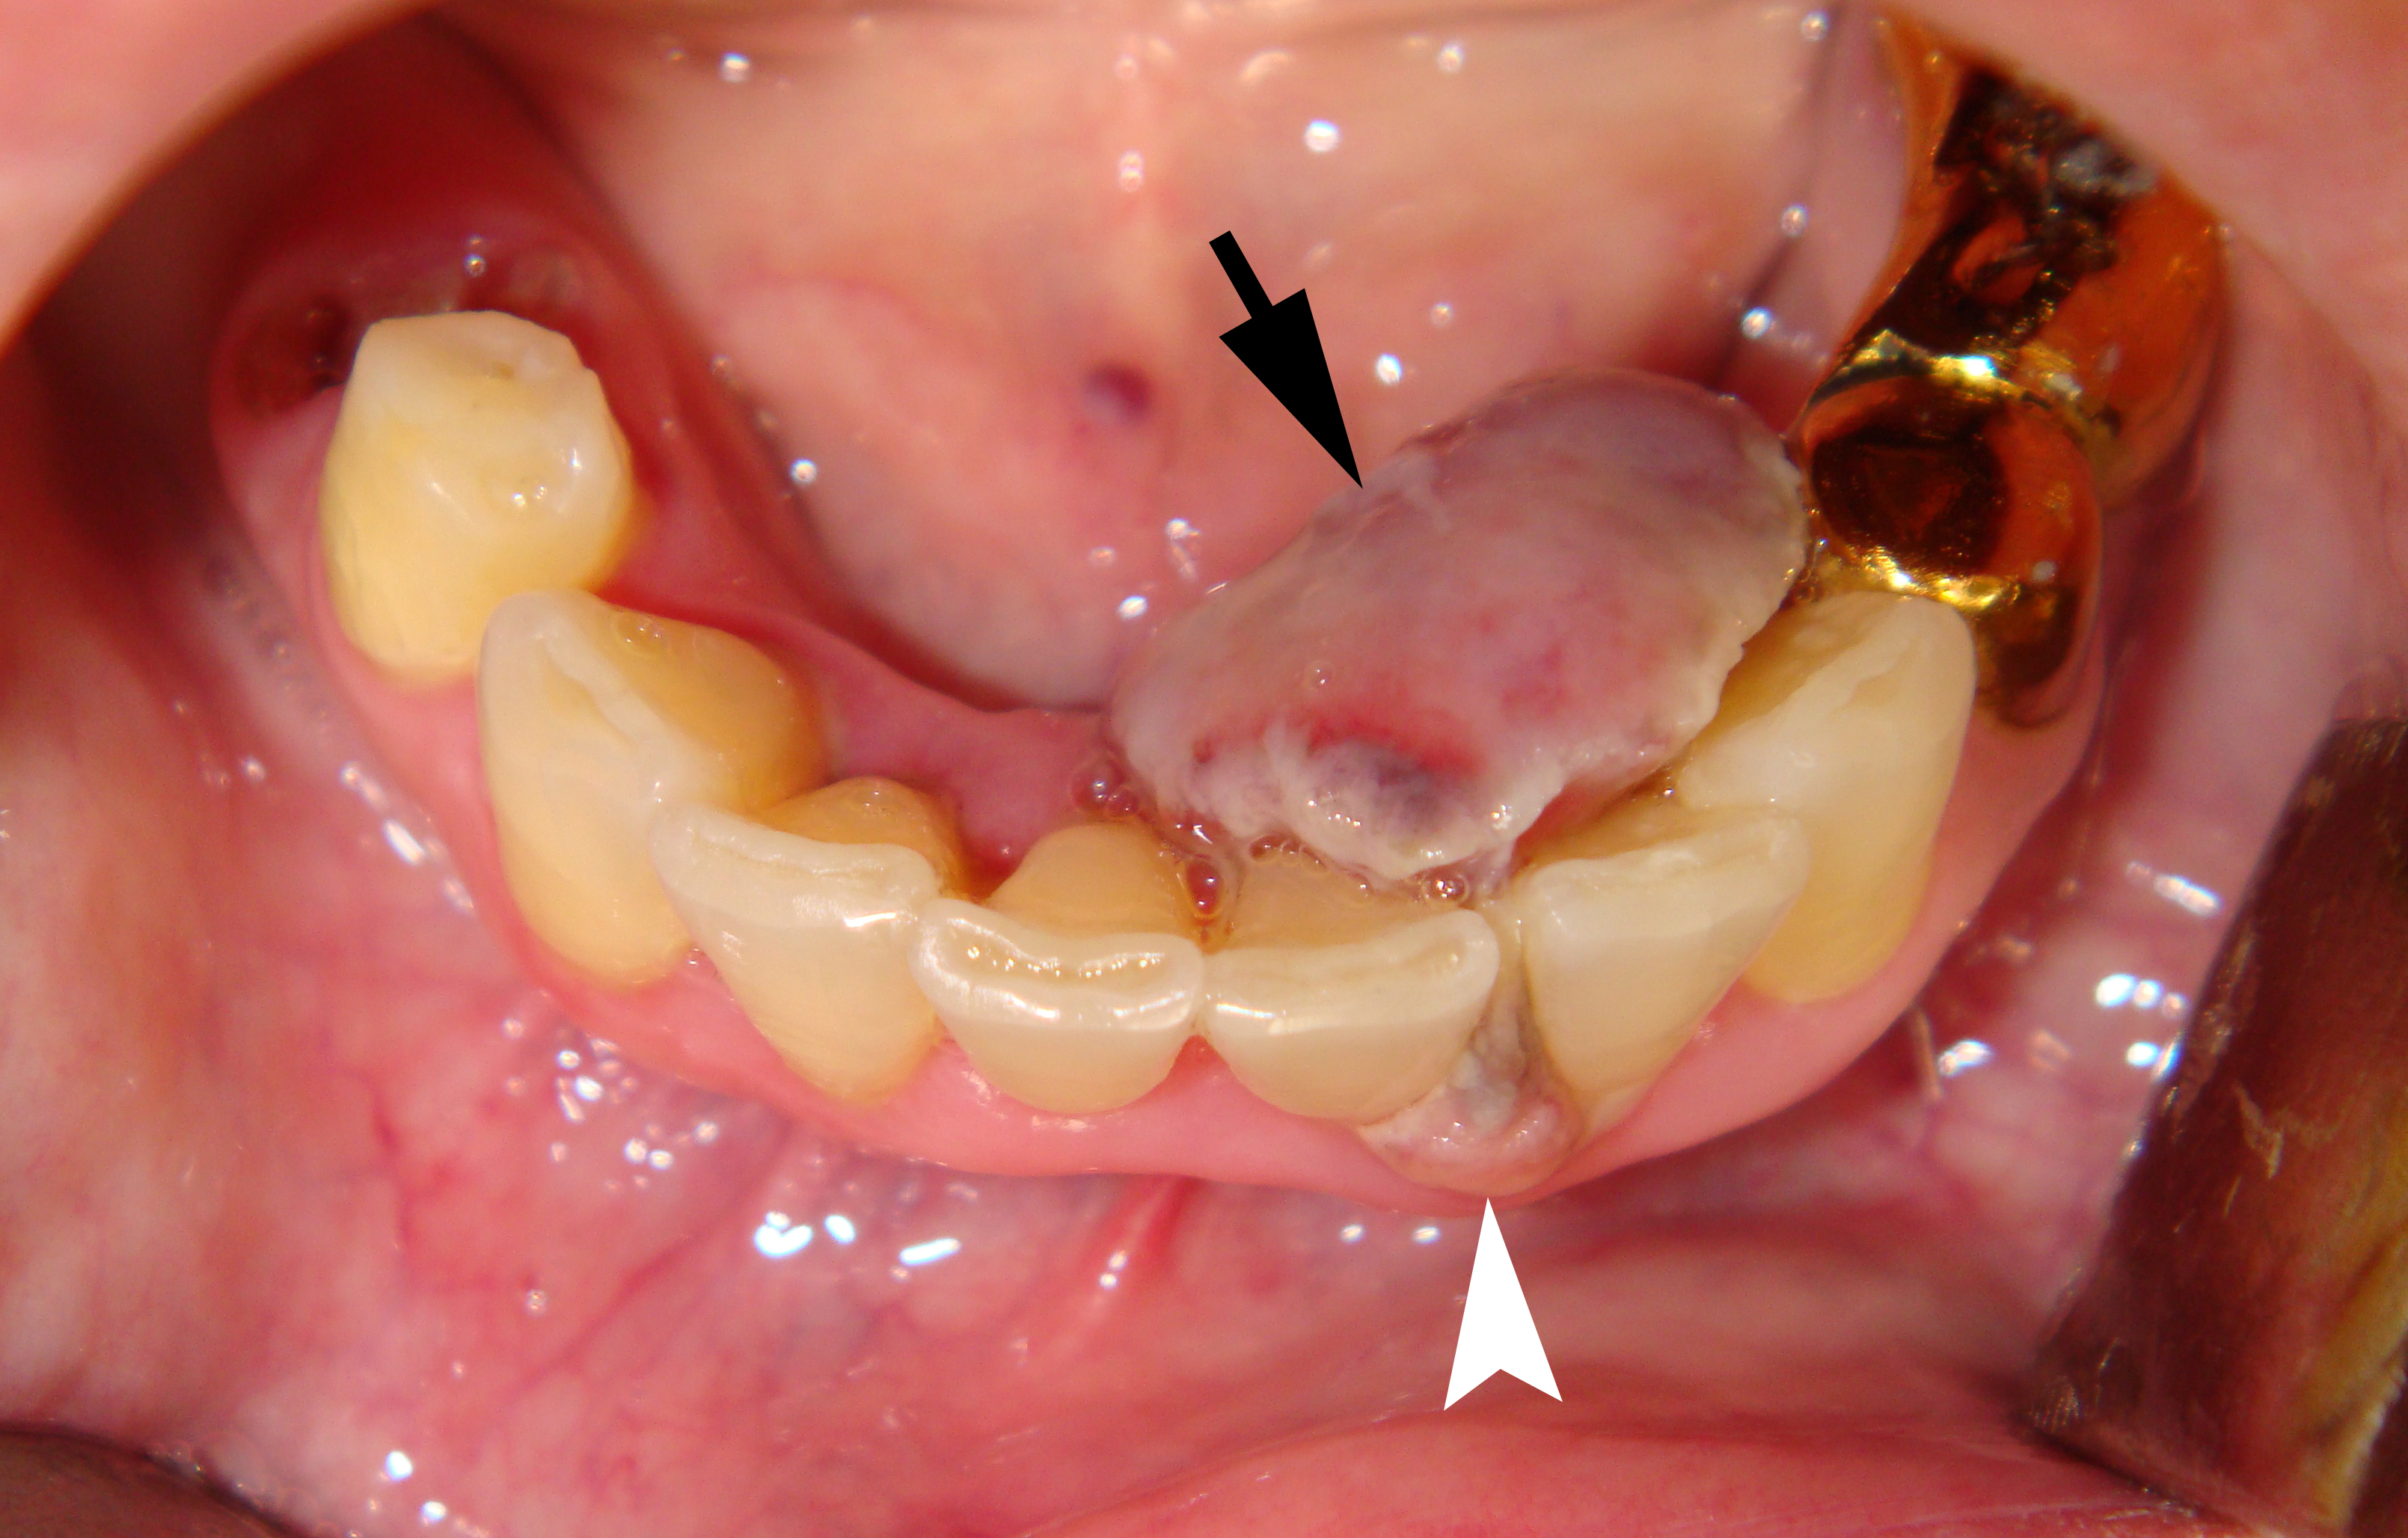

Clinical examination revealed the presence of a neoplasm on the lingual side of the alveolar process of the mandible that had grown vestibularly between the left central and lateral incisors (Fig 1). The neoplasm was mushroom-shaped, pale pink in color, elastic upon palpation, and had a pedicle. The mucosa adjacent to the neoplasm is unchanged in color and structure. The neoplasm measured 1.8 x 1.1 x 1.2 cm at the lingual aspect of the lower teeth and 0.34 x 0.38 cm at the vestibular aspect.

Orthopantomography (Fig 2) showed a minor area of ​​alveolar ridge resorption in the area between the lower left lateral incisor and canine.